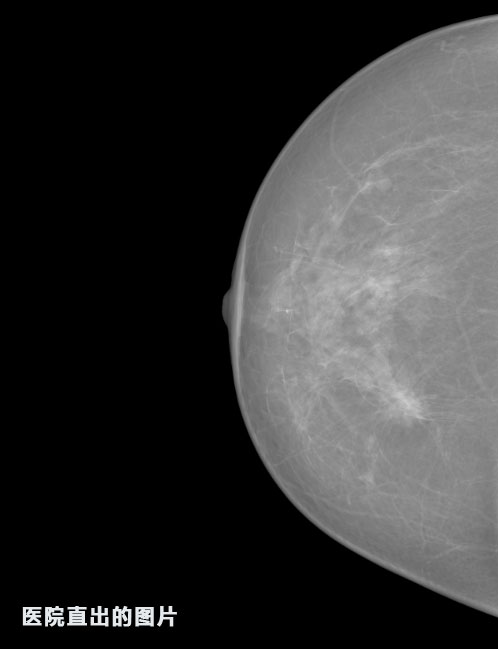

英特健康A(chǔ)I深度學(xué)習(xí)醫(yī)療圖像識(shí)別系統(tǒng)案例_乳腺

01.jpg